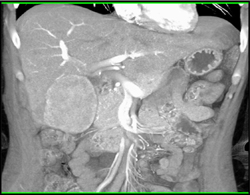

Cholangiocarcinoma